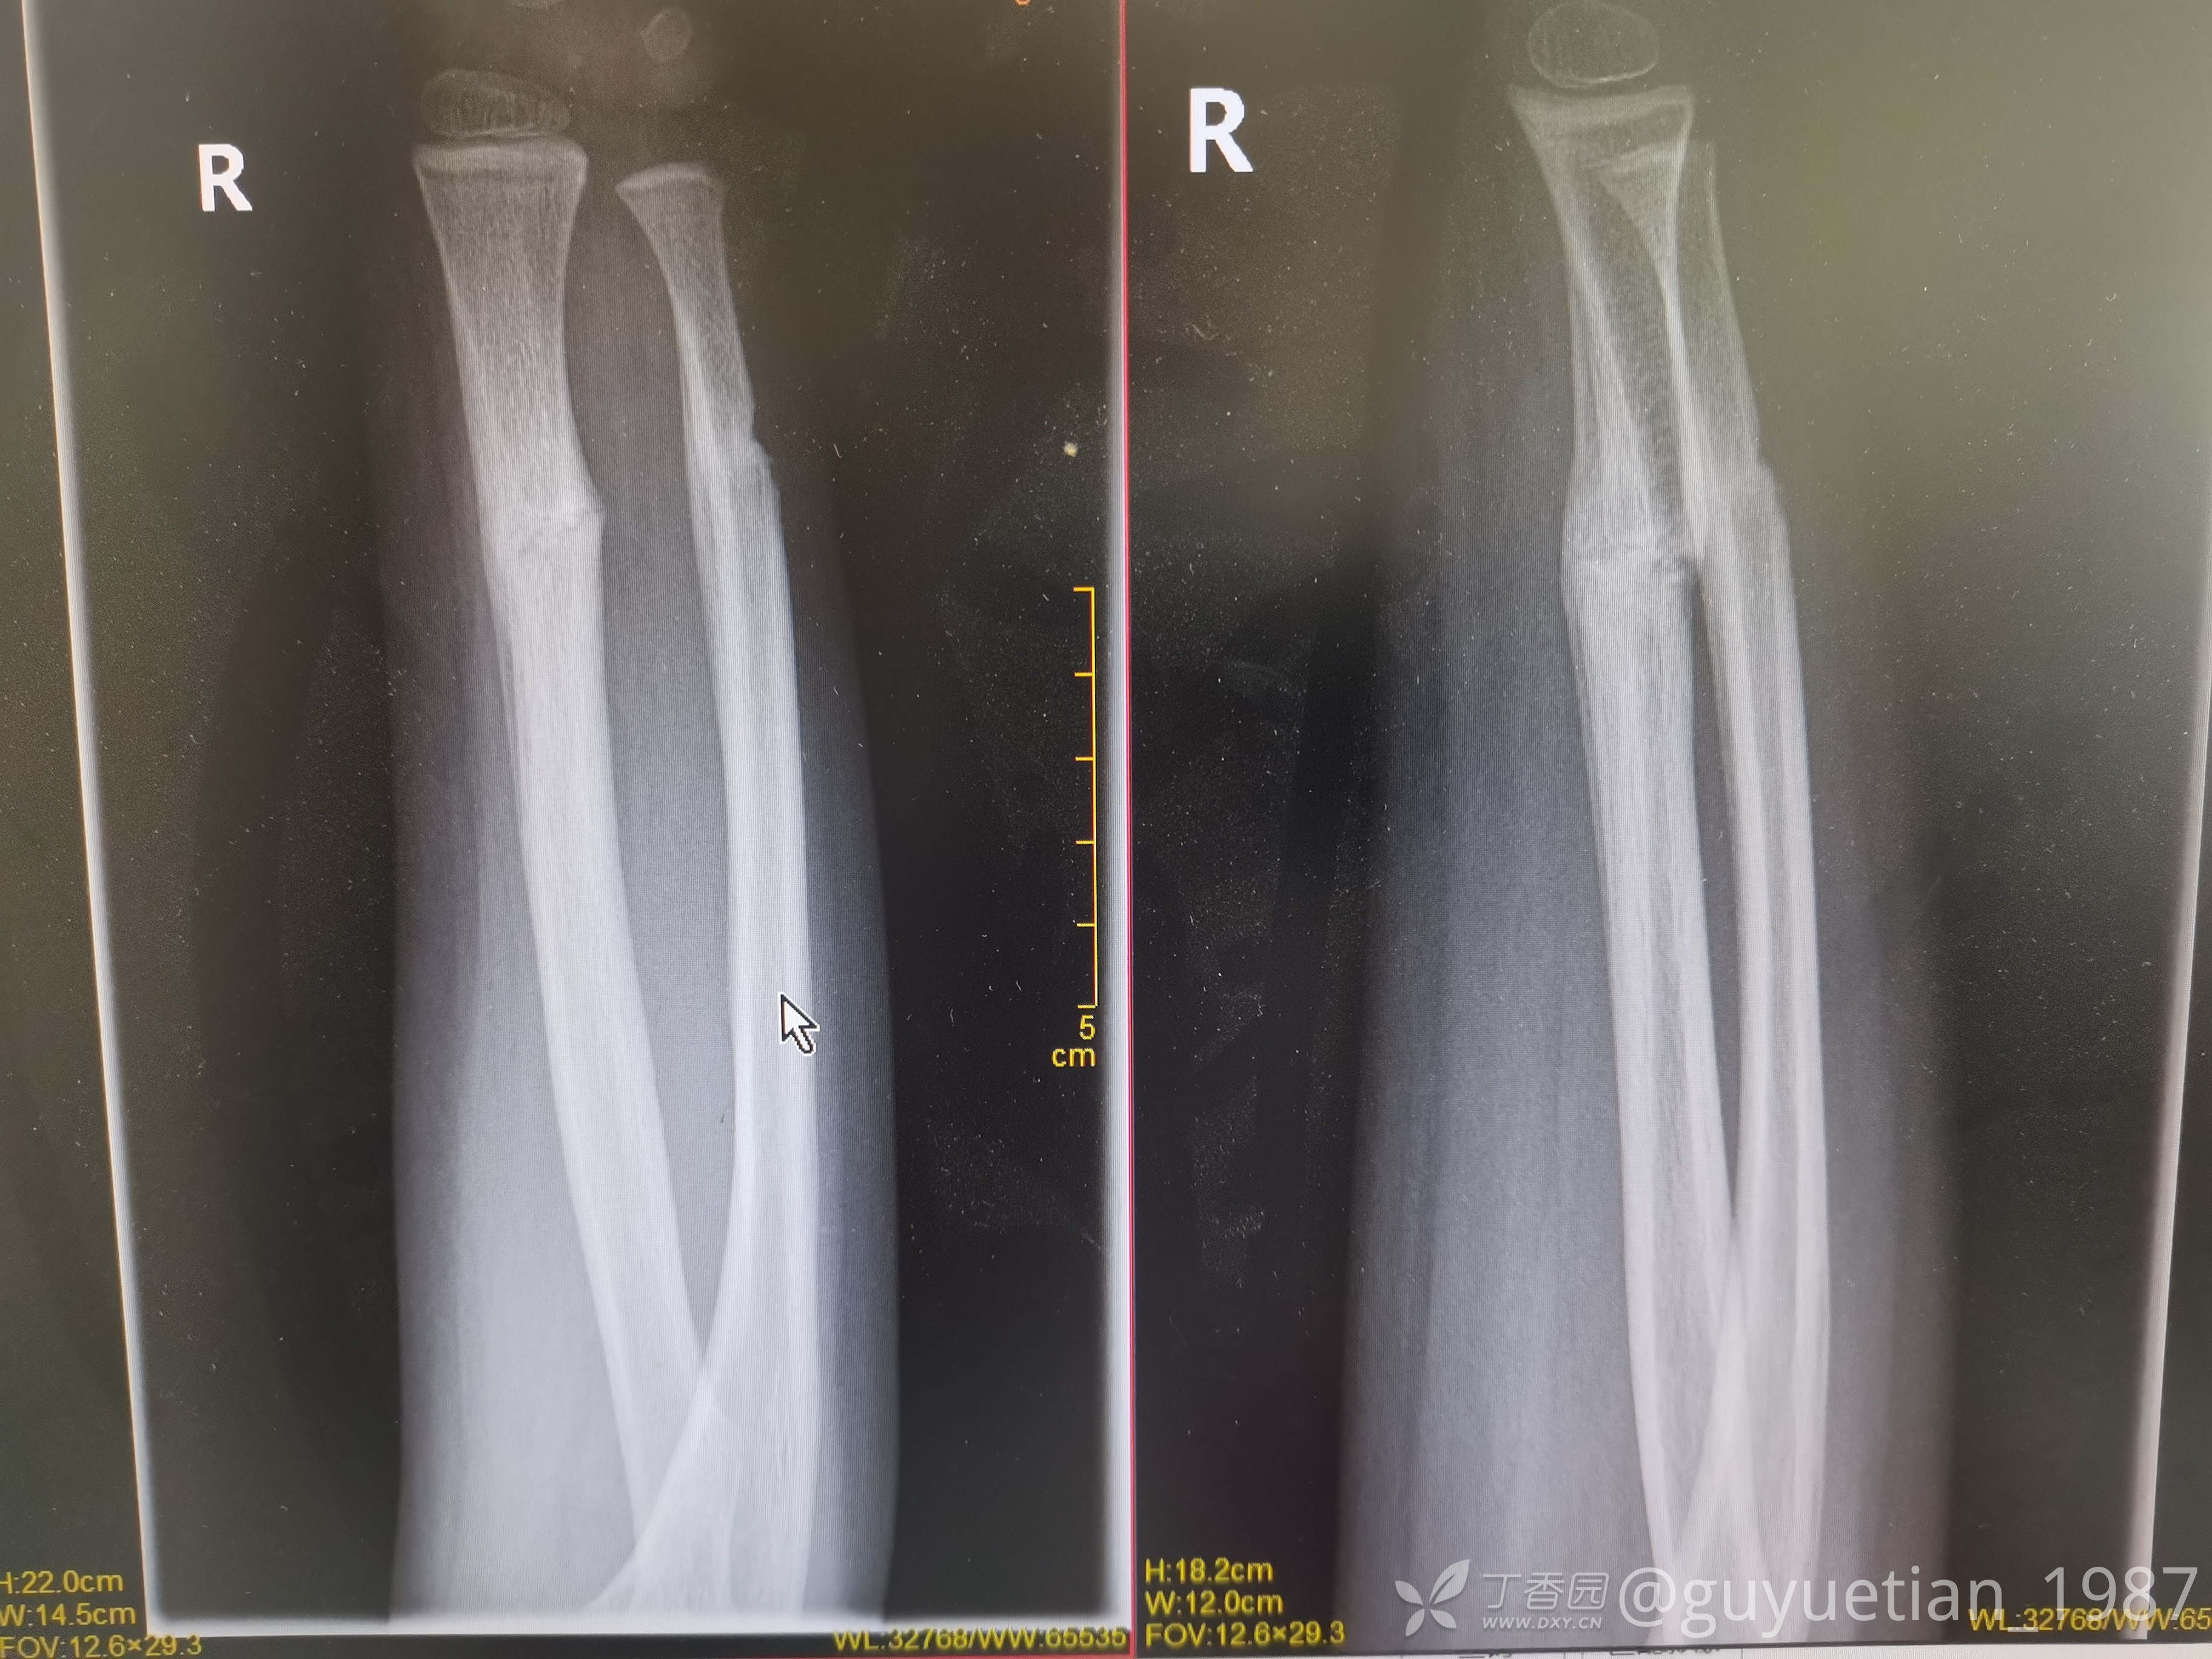

5周后复诊,解除夹板固定。塑形可以,外观正常。

7周后复诊